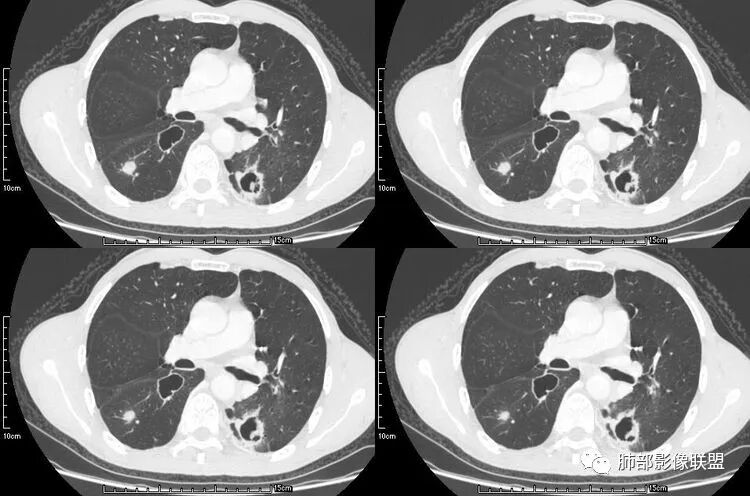

患者老年男性,咳嗽、咳痰、痰中带血伴胸闷2月余。长期大量吸烟史。查肝肾功能、血糖、血脂、心肌酶、电解质、血沉、C反应蛋白、抗“O”、类风湿因子、抗核抗体谱无明显异常。肿瘤标志物提示NSE、CYFRA21-1稍升高。胸部CT:肺气肿背景,左肺下叶后基底段不规则肿块影,见支气管截断,内见大片状低密度区及部分血管影,增强轻度强化,远端空洞形成。双肺多发不规则实性结节影、见毛刺、胸膜牵拉及血管集束,结节内见空洞形成,部分可见血管影,多位于胸膜下。双肺见多发肺大泡。综合考虑左下肺恶性病变并双肺转移。鳞癌或淋巴瘤可能。鉴别血管炎性病变及真菌感染。

本病例左肺下叶肿块,有深分叶、毛刺、胸膜牵拉凹陷、支气管截断及纵隔内淋巴结肿大等征象,都均支持病灶为恶性,如腺癌,而且叶间裂的多发结节也提示是腺癌来源可能大;双肺多发结节、肿块,大部分病灶有分叶、毛刺及胸膜凹陷的恶性征象,与原发肿瘤本身的性质有关,所以应该与左肺下叶肿块同源,而且双肺多发病灶内空洞也具有多样性;

此病例中空洞形态多样,内壁不光整,有分隔影,周围未见明显卫星灶及钙化灶,结核不太符合;患者病史慢性病史,无明显发热,缺乏中毒临床表现,急性感染基本排除;各种中性粒细胞胞浆抗体阴性,没有鼻窦炎,肾脏等病史,基本排除血管炎;霉菌性空洞常见于免疫机能低下者, 常为空洞、肺炎、伴“ 晕圈”征的结节及支气管扩张合并存在。